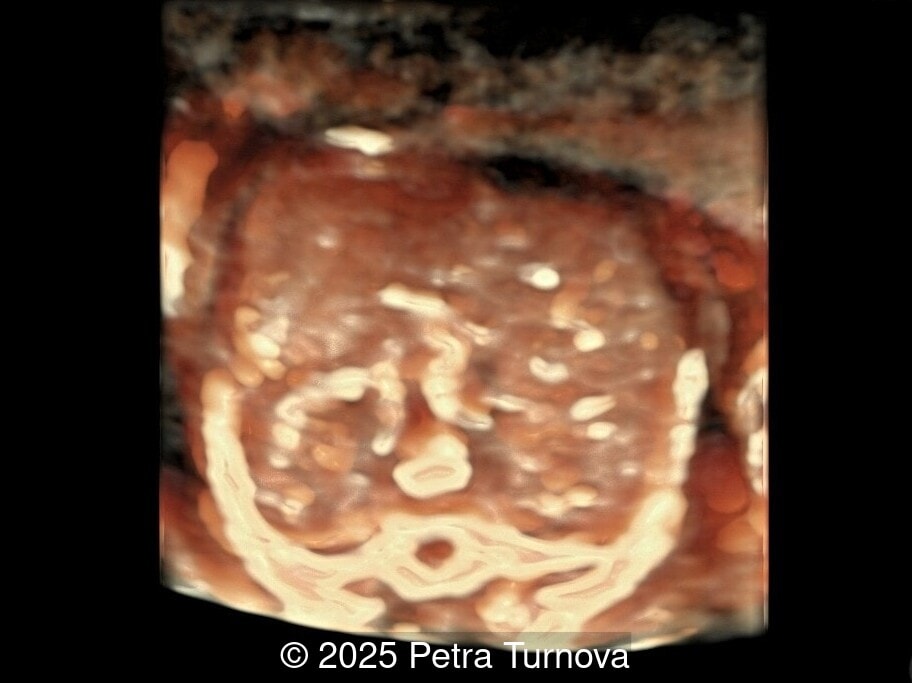

Ultrasound examination revealed abnormal subcutaneous tissue and abnormal nuchal fold highly suggestive of trisomy 21. In addition, a marked hepatomegaly was noted, with the liver appearing diffusely hyperechogenic. No ascites or signs of hydrops were present.

Given the constellation of findings, Trisomy 21 with associated hematologic involvement, most likely transient myeloproliferative disorder, was suspected. The patient underwent amniocentesis, which confirmed Trisomy 21. After multidisciplinary counseling, the patient opted for termination of pregnancy, which was performed at 20 weeks gestation. A fetal autopsy was performed. External examination confirmed facial dysmorphism characteristic of Down syndrome, including a flat nasal bridge and epicanthic folds. Internal examination revealed marked hepatosplenomegaly with the liver weighing approximately 2.5 times the expected weight for gestational age and demonstrated diffuse pale nodularity. Histopathologic examination showed massive extramedullary hematopoiesis with numerous immature megakaryoblasts, large atypical nuclei, and frequent mitotic figures within the hepatic sinusoids and portal areas. Similar infiltrates were present in the splenic red pulp and occasionally in the bone marrow, confirming the diagnosis of transient myeloproliferative disorder in association with Trisomy 21. This case underscores the importance of recognizing fetal hepatomegaly with dysmorphic features of Trisomy 21 as a potential marker of transient myeloproliferative disorder, prompting targeted cytogenetic testing and appropriate counseling.

From the prenatal diagnostic viewpoint, the combination of trisomy 21 and hepatosplenomegaly on ultrasound should prompt suspicion of transient myeloproliferative disorder [1,4]. The disease can manifest as fetal hepatosplenomegaly, hydrops fetalis, polyhydramnios, or placentomegaly [4,5]. The enlarged fetal liver, often hyperechogenic, reflects massive extramedullary hematopoiesis and infiltration by megakaryoblasts. Splenic enlargement and occasional ascites or pericardial effusion may accompany the presentation. Doppler studies may show increased middle cerebral artery peak systolic velocity due to fetal anemia [5,6]. Cytologically, peripheral blood and fetal liver aspirates reveal increased circulating blasts, often with megakaryoblastic morphology (irregular nuclei, cytoplasmic blebs, and platelet peroxidase positivity). Bone marrow may be normocellular or show hypocellularity with increased immature megakaryocytes [2].